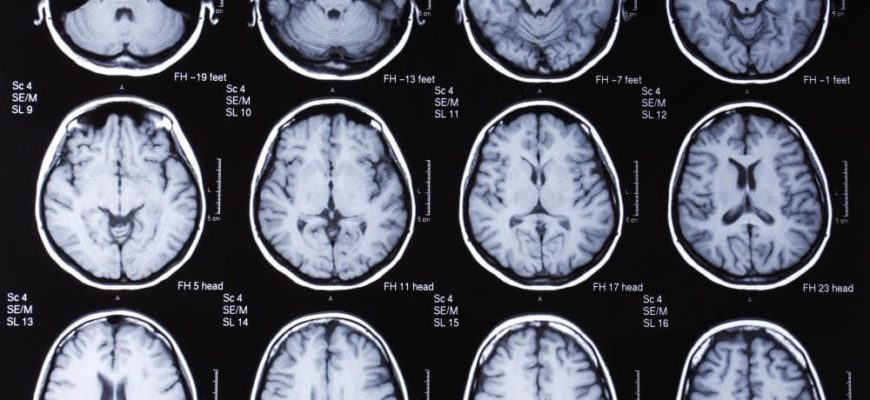

• МРТ — основана на действии магнитного поля, которое воздействует на атомы водорода в организме. Они меняют свой потенциал, а специальные сенсоры устройства улавливают сигнал и преобразуют его в изображение. На фотографиях показаны структуры головного мозга и патологические структуры. Во время процедуры пациент находится в капсуле аппарата, ему запрещается совершать малейшие движения, что снижает качество изображения.

Из сравнения видно, что МРТ отличается тем, что показывает органические изменения в головном мозге, ЭЭГ — физиологические процессы.

Магнитно-резонансные изображения позволяют детально рассмотреть органическую патологию, не могут выявить физиологические нарушения.